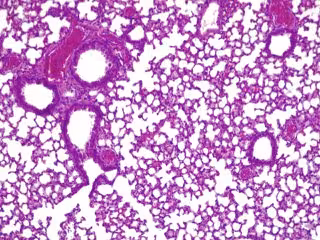

Pulmones de ratón con 'pildora viva' activa combatiendo 'presudomonas aerugionosa'

Pulmones de ratón con 'pildora viva' activa combatiendo 'presudomonas aerugionosa' - CGR/PULMOBIOTICS

La 'píldora viva' duplicó la tasa de supervivencia del ratón en comparación con la opción de no usar ningún tratamiento, y la administración de una única dosis alta no mostró signos de toxicidad en los pulmones.